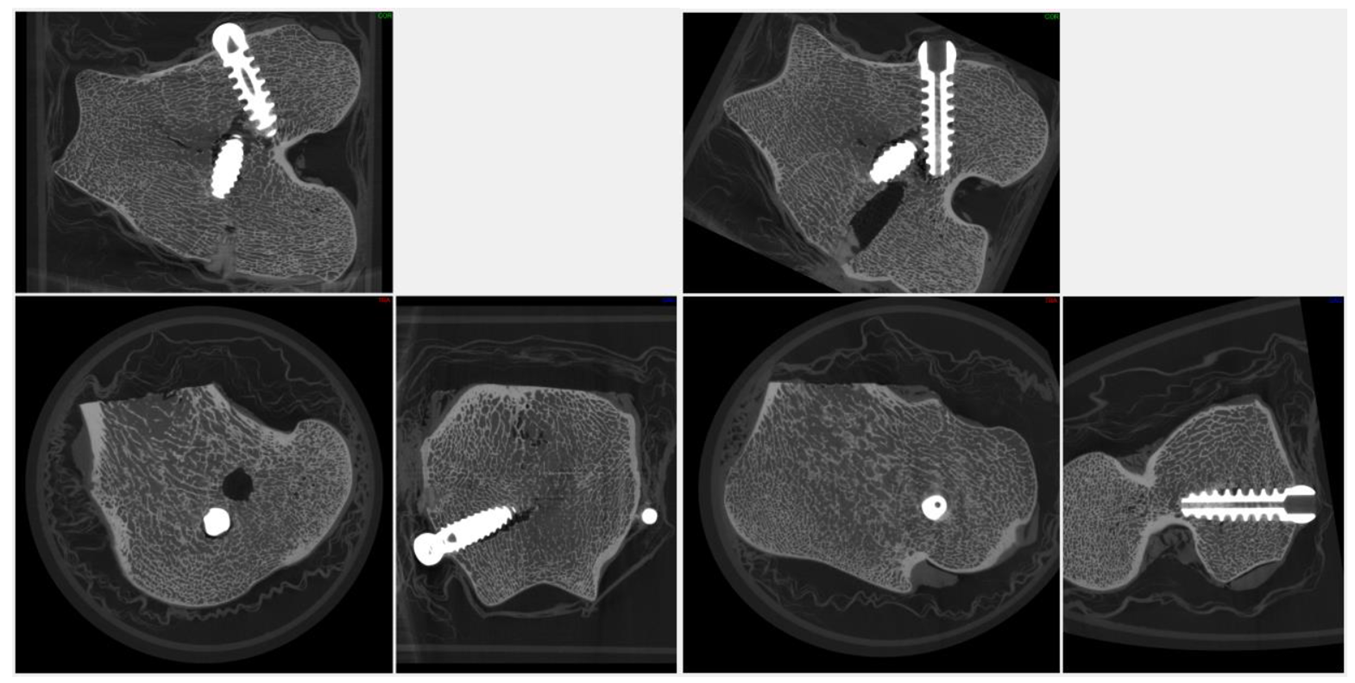

3.3 Imaging Dense Materials and Metal Implants

Dental micro-CT frequently involves imaging dense, highly attenuating materials such as titanium implants, stainless steel instruments, and zirconia restorations. These materials increase beam hardening and streak artifacts, which can obscure adjacent bone or cement layers if not properly managed. High tube voltages, appropriate spectral filtration, increased projection counts, and optimized reconstruction parameters are therefore essential.

When optimized, micro-CT enables simultaneous visualization of metal components and surrounding bone microarchitecture, supporting quantitative assessment of osseointegration and material performance. Advanced acquisition modes such as helical scanning can further reduce artifacts in challenging geometries, expanding the range of dental applications accessible to micro-CT.

High-attenuation dental materials, including titanium implants and zirconia restorations, generate pronounced beam hardening and photon starvation artifacts that appear as streaking and grayscale distortion in CT imaging; mitigation of these effects requires elevated tube voltages and appropriate spectral filtration to harden the X-ray beam, and can be further improved through helical (spiral) scanning geometries that reduce angular undersampling and distribute metal-induced artifacts across the reconstructed volume (Barrett & Keat, 2004).

Micro-CT provides a direct, three-dimensional means of quantifying peri-implant bone microarchitecture. By defining standardized volumes of interest around the implant surface, researchers can measure bone volume fraction, trabecular thickness, separation, and connectivity density. These parameters correlate with mechanical stability and load transfer capacity, supporting both fundamental research and preclinical evaluation of implant designs (Pauwels et al., 2013; Bouxsein et al., 2010).

| Bone volume fraction (BV/TV) | % or unitless ratio | Ratio of bone volume to total volume within a defined peri-implant region of interest | Primary indicator of osseointegration and peri-implant bone support | Requires consistent VOI definition; sensitive to thresholding and beam hardening correction |

| Trabecular thickness (Tb.Th) | µm | Mean thickness of trabecular elements surrounding the implant | Reflects mechanical competence and load-bearing capacity of peri-implant bone | Influenced by voxel size; partial-volume effects must be minimized |

| Trabecular separation (Tb.Sp) | µm | Mean distance between trabeculae | Indicates porosity and space available for vascularization | Requires accurate bone segmentation; sensitive to noise |

| Trabecular number (Tb.N) | 1/mm | Number of trabeculae per unit length | Describes trabecular network density | Assumes isotropic trabecular structure within VOI |

| Connectivity density (Conn.D) | 1/mm³ | Measure of trabecular network connectivity per unit volume | Relates to load distribution and structural redundancy | Sensitive to segmentation errors and VOI size |

| Bone–implant contact (BIC) | % | Fraction of implant surface directly contacting bone | Indicator of primary and secondary implant stability | Metal artifacts must be minimized; surface definition depends on resolution |

| Peri-implant bone density | mg HA/cm³ | Mean mineral density of bone adjacent to the implant | Correlates with bone quality and mechanical strength | Requires calibrated grayscale values using HA phantoms |

| Bone ingrowth depth | mm | Radial extent of bone penetration toward or into implant features | Relevant for porous or threaded implant designs | Dependent on implant geometry and VOI alignment |